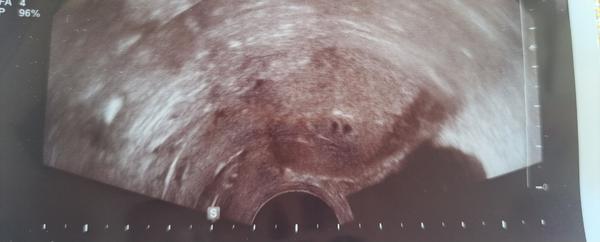

@loylii v centru mi lhali a tvrdili, že jsou mono-bi, abych dala pokoj. I když odborníkovi muselo být jasné, že jsou bi-bi. Ve čtvrtek jsem byla na prvotrimestrálním screeningu, kde mi potvrdili, že jsou bi-bi, že mají placenty a dokonce dost daleko od sebe. Jedna je na přední a druhá na zadní straně. Bojím se chyby - lidského faktoru, že mi vložili cizí embrya.

@kate1_1 no je to zvláštní teda cely😃.. já měla taky dvě embrya. Jedno na přední straně a druhy na zadní. Daleko od sebe. Jedno nahoře a druhy až dole u čípku. Tak bylo hned jasne na prvním UTZ, ze jsou bibi. Ani na jednu fotku se nevesli, jak byli od sebe daleko.